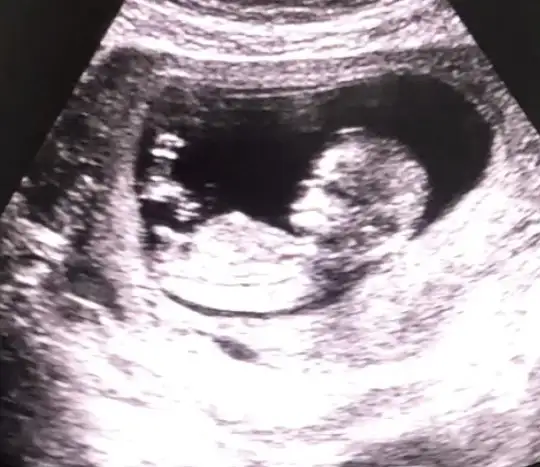

Kızlar selamm. Doktorum 16. Haftadan önce cinsiyet söylemiyor. Fotoğraf bugünkü kontrolden. 12+3'teyiz. Tahmin rica edebilir miyim

Eklentiler

• 58DCD844-4A93-4D64-A785-F0C5FF76757B.webp

22,7 KB · Görüntüleme: 76